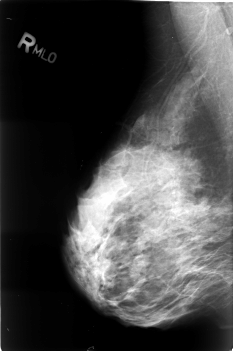

B_3033_1.RIGHT_MLO

RIGHT_MLO LINES 4552 PIXELS_PER_LINE 3040 BITS_PER_PIXEL 12 RESOLUTION 50 NON_OVERLAY